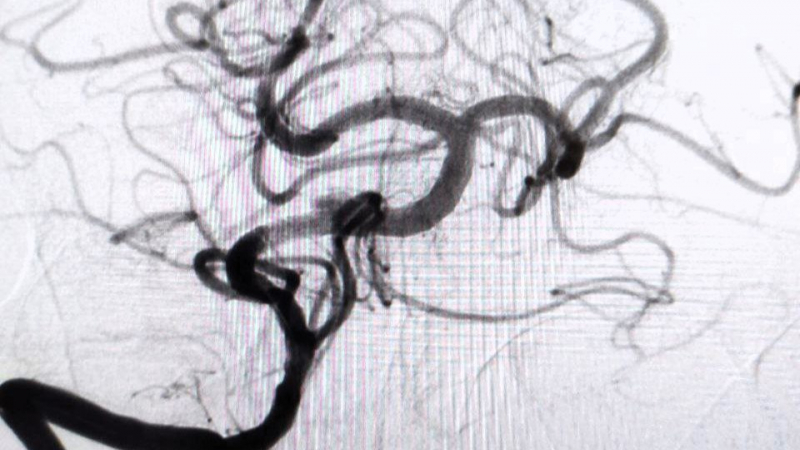

По словам заведующего отделением рентгенохирургических методов диагностики и лечения РСЦ Антона Аналеева, причиной стало образование атеросклеротической бляшки, перекрывшей главную артерию, снабжающую кровью ключевые участки мозга.

Благодаря вовремя поставленному диагнозу пациенту экстренно провели операцию, в ходе которой удалили тромб, а также установили стент.